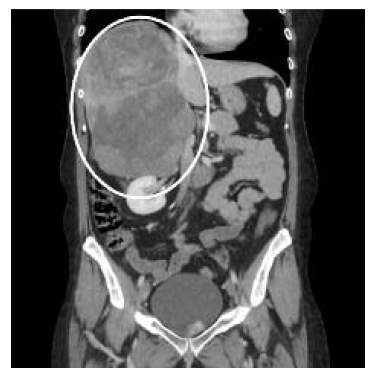

Em janeiro/2023, a utente recorre novamente a consulta com os resultados dos exames. Do estudo efetuado, a destacar MAPA 24 h com “hipertensão arterial sustentada e perfil tensional não dipper”. A ecografia renal apresentava “volumosa massa em íntimo contacto com o bordo posterior do lobo direito hepático medindo cerca de 20 cm de maior eixo incompletamente caracterizada por esta técnica”. A utente trazia já uma tomografia computorizada, que foi realizada imediatamente após a ecografia, e que revelou “no hipocôndrio direito, em relação com o lobo hepático direito, identifica-se volumosa massa heterogénea com áreas de captação na fase arterial e nas fases tardias, demonstrando também algumas áreas hipocaptantes que podem corresponder a áreas necróticas, medindo aproximadamente 16,2 × 14,6 cm de maior eixos axiais e 20,2 cm de eixo longitudinal (...) não se define a glândula suprarrenal pelo que a referida massa pode ter origem suprarrenal ou hepática (...). No segmento hepático VII identificam-se três nódulos hipodensos com 26 mm, 17 mm e 16 mm e no segmento VI um nódulo, cujo comportamento no estudo dinâmico não permite a sua caracterização” (Figuras 1 e 2).

Figura 2 Carcinoma da suprarrenal em tomografia computorizada (corte coronal) - assinalado com círculo.